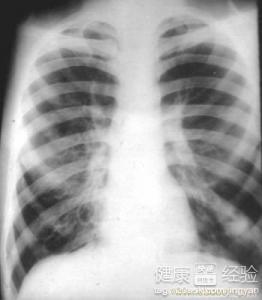

支氣管炎是一種常見的呼吸系統(tǒng)疾病,其癥狀包括咳嗽、咳痰、呼吸急促等,許多患者關(guān)心的問題是:支氣管炎能自愈嗎?本文將詳細(xì)解析支氣管炎的類型、癥狀、治療方法以及能否自愈的問題,幫助患者更好地了解并應(yīng)對這一疾病。

支氣管炎是指氣管、支氣管黏膜及其周圍組織的炎癥,根據(jù)其發(fā)病的急緩,可分為急性支氣管炎和慢性支氣管炎,急性支氣管炎通常由于病毒、細(xì)菌等感染引起,癥狀明顯且病程較短;而慢性支氣管炎則由于長期吸煙、空氣污染等因素導(dǎo)致,癥狀持續(xù)較長時間,易反復(fù)發(fā)作。